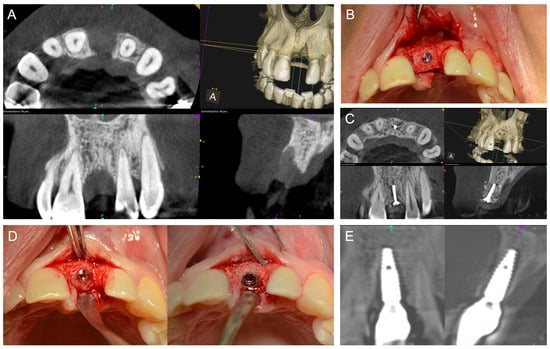

- CAD/CAM ABB—Customized, patient-specific CAD/CAM-manufactured allogeneic cancellous bone block (maxgraft® bonebuilder; botiss), designed from Cone-beam computed tomography (CBCT) data and fixed with titanium screws (Figure 4).